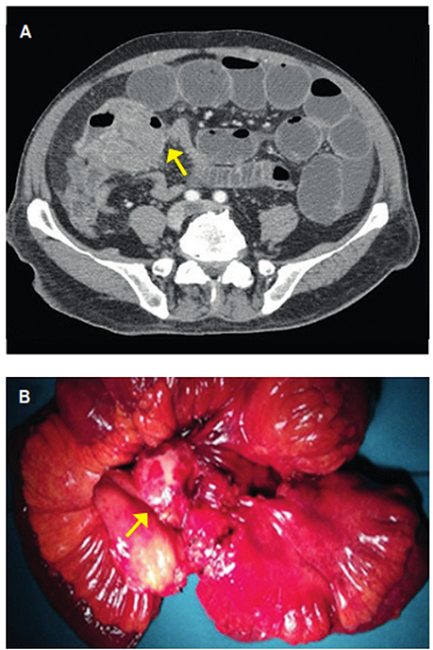

Una semana tras el ingreso empeora clínicamente, con acidosis metabólica y criterios de sepsis. Se realiza nuevo TC (Figura 3) hallando tumoración abscedada que condiciona cuadro oclusivo y liquido libre que sugiere sufrimiento de asa intestinal. Se interviene de urgencia, encontrando tumoración en íleon terminal que compromete dos asas intestinales, una de ellas torsionada sobre sí misma causando la oclusión. Se practica resección intestinal con la tumoración en bloque, con evolución postoperatoria favorable. La anatomía patológica confirmó metástasis de melanoma, infiltrante y ulcerado, alcanzando todas las capas de la pared, con márgenes libres.